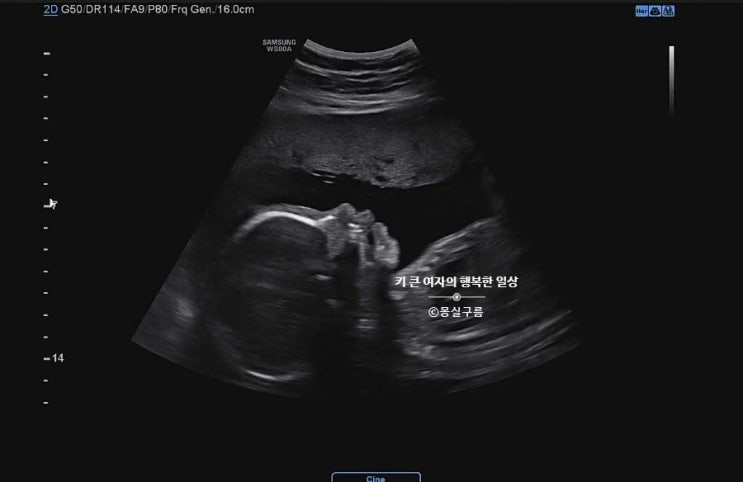

임신 후기 28주차 증상 / 송파고은빛 입체초음파 할인

임신 28주차 자궁수축 이벤트가 있어서그런지 순식간에 찾아온 듯한 임신 28주차. 28주차부터 임신 후기에 ...